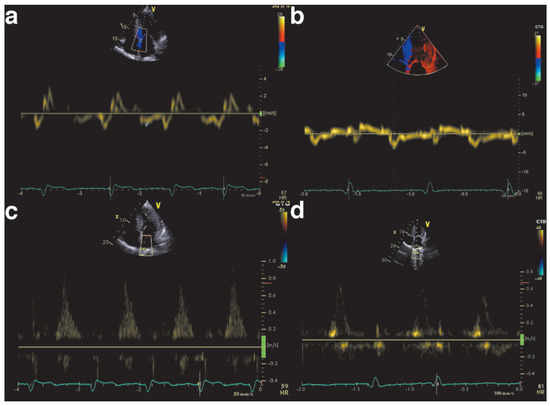

The Eustachian ridge is ablated as part of the cavotricuspid isthmus (CTI) involved in typical atrial flutter (AFL) ablation, but is itself rarely an arrhythmogenic focus. We report a case of a patient with dual tachycardia involving the CTI area....